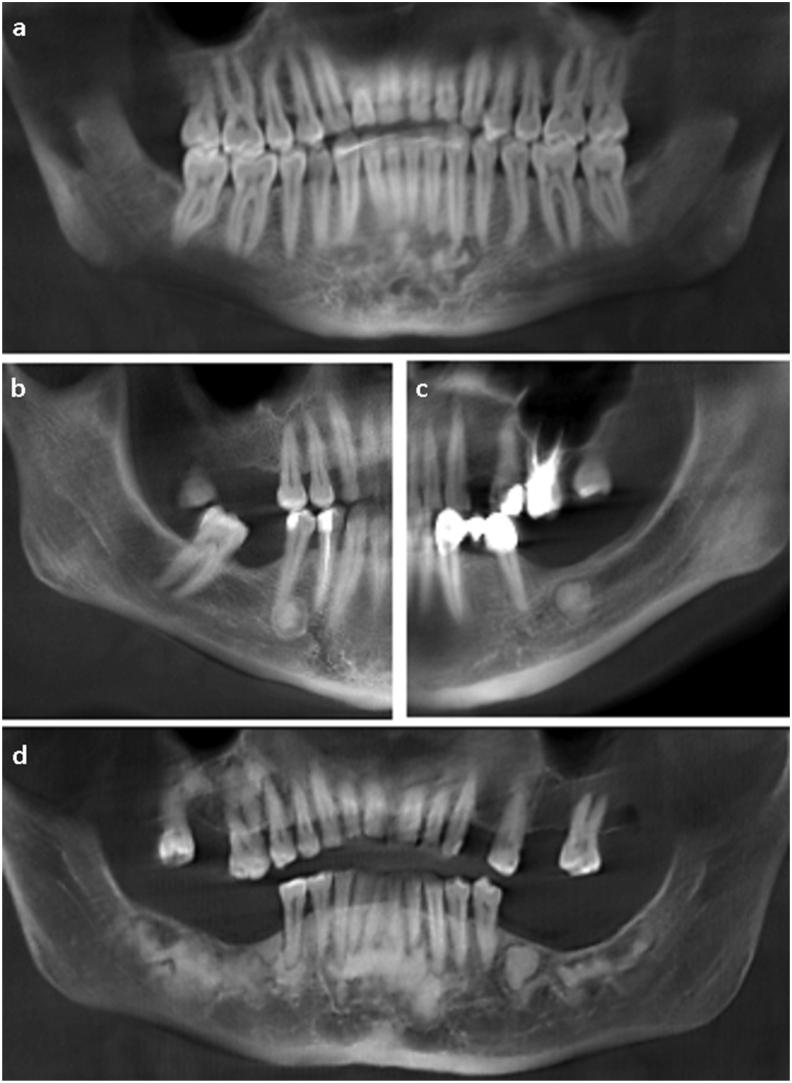

BACKGROUND/PURPOSE: Radiological examination is indispensable in the diagnosis and follow-up of cemento-osseous dysplasia (COD). The aim of this retrospective study was to describe a series of COD cases, identify the frequencies of COD subtypes, and investigate the demographic and radiological characteristics in relation to subtypes.

Cone beam computed tomography (CBCT) images/reports of patients with a diagnosis of COD were included in the study. The data collected included information on the age, sex, subtype of COD, location of COD, and region involved. Information regarding the internal density, effects on surrounding structures, and presence of concomitant lesions was also collected. The data obtained were evaluated statistically.

The study group included CBCT images of 142 patients (130 females (91.5%) and 12 males (8.5%)) with a mean age of 46.97 ± 10.57 years. The mandible was involved in almost all cases (99.3%). The most common subtype was florid COD (51.4%) and lesions with hyperdense internal density (81.7%) were more commonly observed. Cortical thinning (78.2%) was a prominent feature. The frequency of root resorption in periapical COD cases (57.1%) was observed to be significantly higher (p < 0.05). All hypercementosis cases were associated with florid subtype (p < 0.05). In a minority of cases (6.3%), the lesions were associated with bone cysts and osteomyelitis.

CBCT images clearly demonstrated the effect of COD lesions on surrounding structures. CBCT is an appropriate imaging modality for the diagnosis and follow-up of COD which is the most common fibro-osseous lesion in clinical practice.

背景/目的:放射学检查在骨化纤维瘤病(COD)的诊断和随访中不可或缺。本回顾性研究的目的是描述一系列COD病例,确定COD亚型的发生率,并研究与亚型相关的人口统计学和放射学特征。

本研究纳入了诊断为COD的患者的锥形束计算机断层扫描(CBCT)图像/报告。收集的数据包括年龄、性别、COD亚型、COD位置和受累区域的信息。还收集了有关内部密度、对周围结构的影响以及伴随病变的存在情况的信息。对获得的数据进行统计学评估。

研究组包括142例患者的CBCT图像(130例女性(91.5%)和12例男性(8.5%)),平均年龄为46.97±10.57岁。几乎所有病例(99.3%)下颌骨均受累。最常见的亚型是弥漫性COD(51.4%),内部密度为高密度的病变(81.7%)更常见。皮质变薄(78.2%)是一个突出特征。根尖周COD病例中牙根吸收的发生率(57.1%)显著更高(p<0.05)。所有牙骨质增生病例均与弥漫性亚型相关(p<0.05)。在少数病例(6.3%)中,病变与骨囊肿和骨髓炎有关。

CBCT图像清楚地显示了COD病变对周围结构的影响。CBCT是临床实践中最常见的纤维-骨病变COD诊断和随访的合适影像学检查方法。